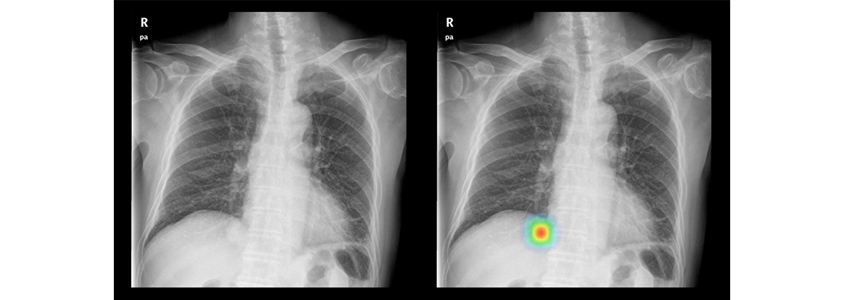

루닛(https://lunit.io/joinus/)의 영상이미지 판독 AI서비스를 예시로 설명해보겠습니다.

AI가 상업화되면서 ‘루닛인사이트’ 처럼 AI가 하나의 제품으로 포장되어 판매됩니다. 이러한 제품이 시중에 판매되기 전에 식약청의 승인허가를 받아야 하죠. 승인허가를 내기 전에 식약청은 제품이 충분하게 실험이 되었는지, 정확도는 높은지에 대한 증명을 합니다. 여기서 정확도가 높은 결과가 나왔을 때, 왜 그렇게 결과가 나왔는지에 대한 해석을 해줘야 합니다. 하지만 아직까지 인간의 해석능력이 AI를 뛰어넘지 못해서 AI가 해석한 것을 볼 수는 있지만 결과가 주는 의미파악은 어려운 상황이죠. 결국, 인간의 능력보다 월등하게 정확한 해석을 해내는 AI가 필요하다고 판단되면, Interpretability AI가 적합한 분야 활용될 수 있을 것 입니다.

Interpretability AI 상업화: 루닛 적용사례 Interpretability AI 상업화 : 루닛 적용사례 & 출처:루닛 홈페이지, 제품소개